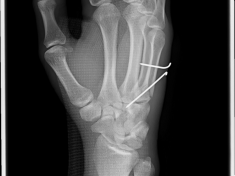

Röntgenbilder